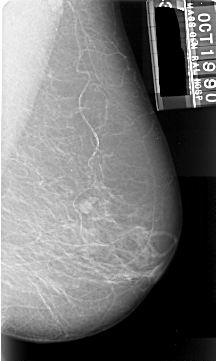

A_1006_1.LEFT_MLO

LEFT_MLO LINES 5461 PIXELS_PER_LINE 3256 BITS_PER_PIXEL 16 RESOLUTION 42 OVERLAY

FILE: A_1006_1.LEFT_MLO.OVERLAY

TOTAL_ABNORMALITIES 1

ABNORMALITY 1

LESION_TYPE MASS SHAPE IRREGULAR MARGINS ILL_DEFINED

ASSESSMENT 4

SUBTLETY 5

PATHOLOGY MALIGNANT

TOTAL_OUTLINES 1

BOUNDARY